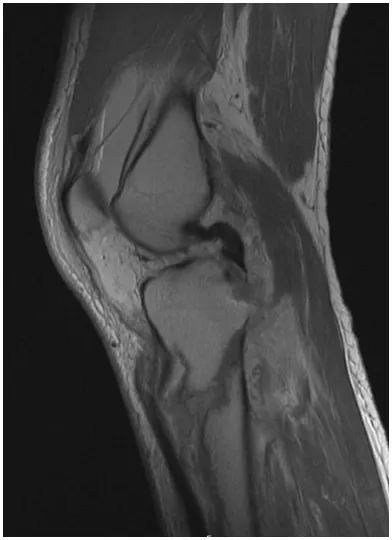

At presentation 1 week after injury, the patient was neurovascularly intact with resolving fracture blisters. The external fixator pin sites showed no evidence of infection. Radiographs showed a complex, largely extra-articular, proximal tibia fracture with dissociation of the tibial tubercle (Fig. 1). Subtle findings of a proximal lateral tibia avulsion fracture (a Segond fracture) and tibial spine comminution raised suspicion for ligamentous knee instability. Diastasis of the proximal fibula from the tibia demonstrated the high energy nature of the trauma. A computed tomography (CT) scan showed the complex proximal tibia fracture with a separate tibial tubercle fragment and confirmed a posterior cruciate ligament (PCL) avulsion fracture and lateral proximal tibia avulsion (Fig. 2). Magnetic resonance imaging (MRI) confirmed a lateral meniscal root tear, disruption of the PCL, proximal tibiofibular capsular ligaments, and moderate posterolateral corner injury (Fig. 3).

Figure 3: MRI shows a secondary deformity of the PCL due to avulsion of the PCL footprint, with a slightly displaced footprint fracture.